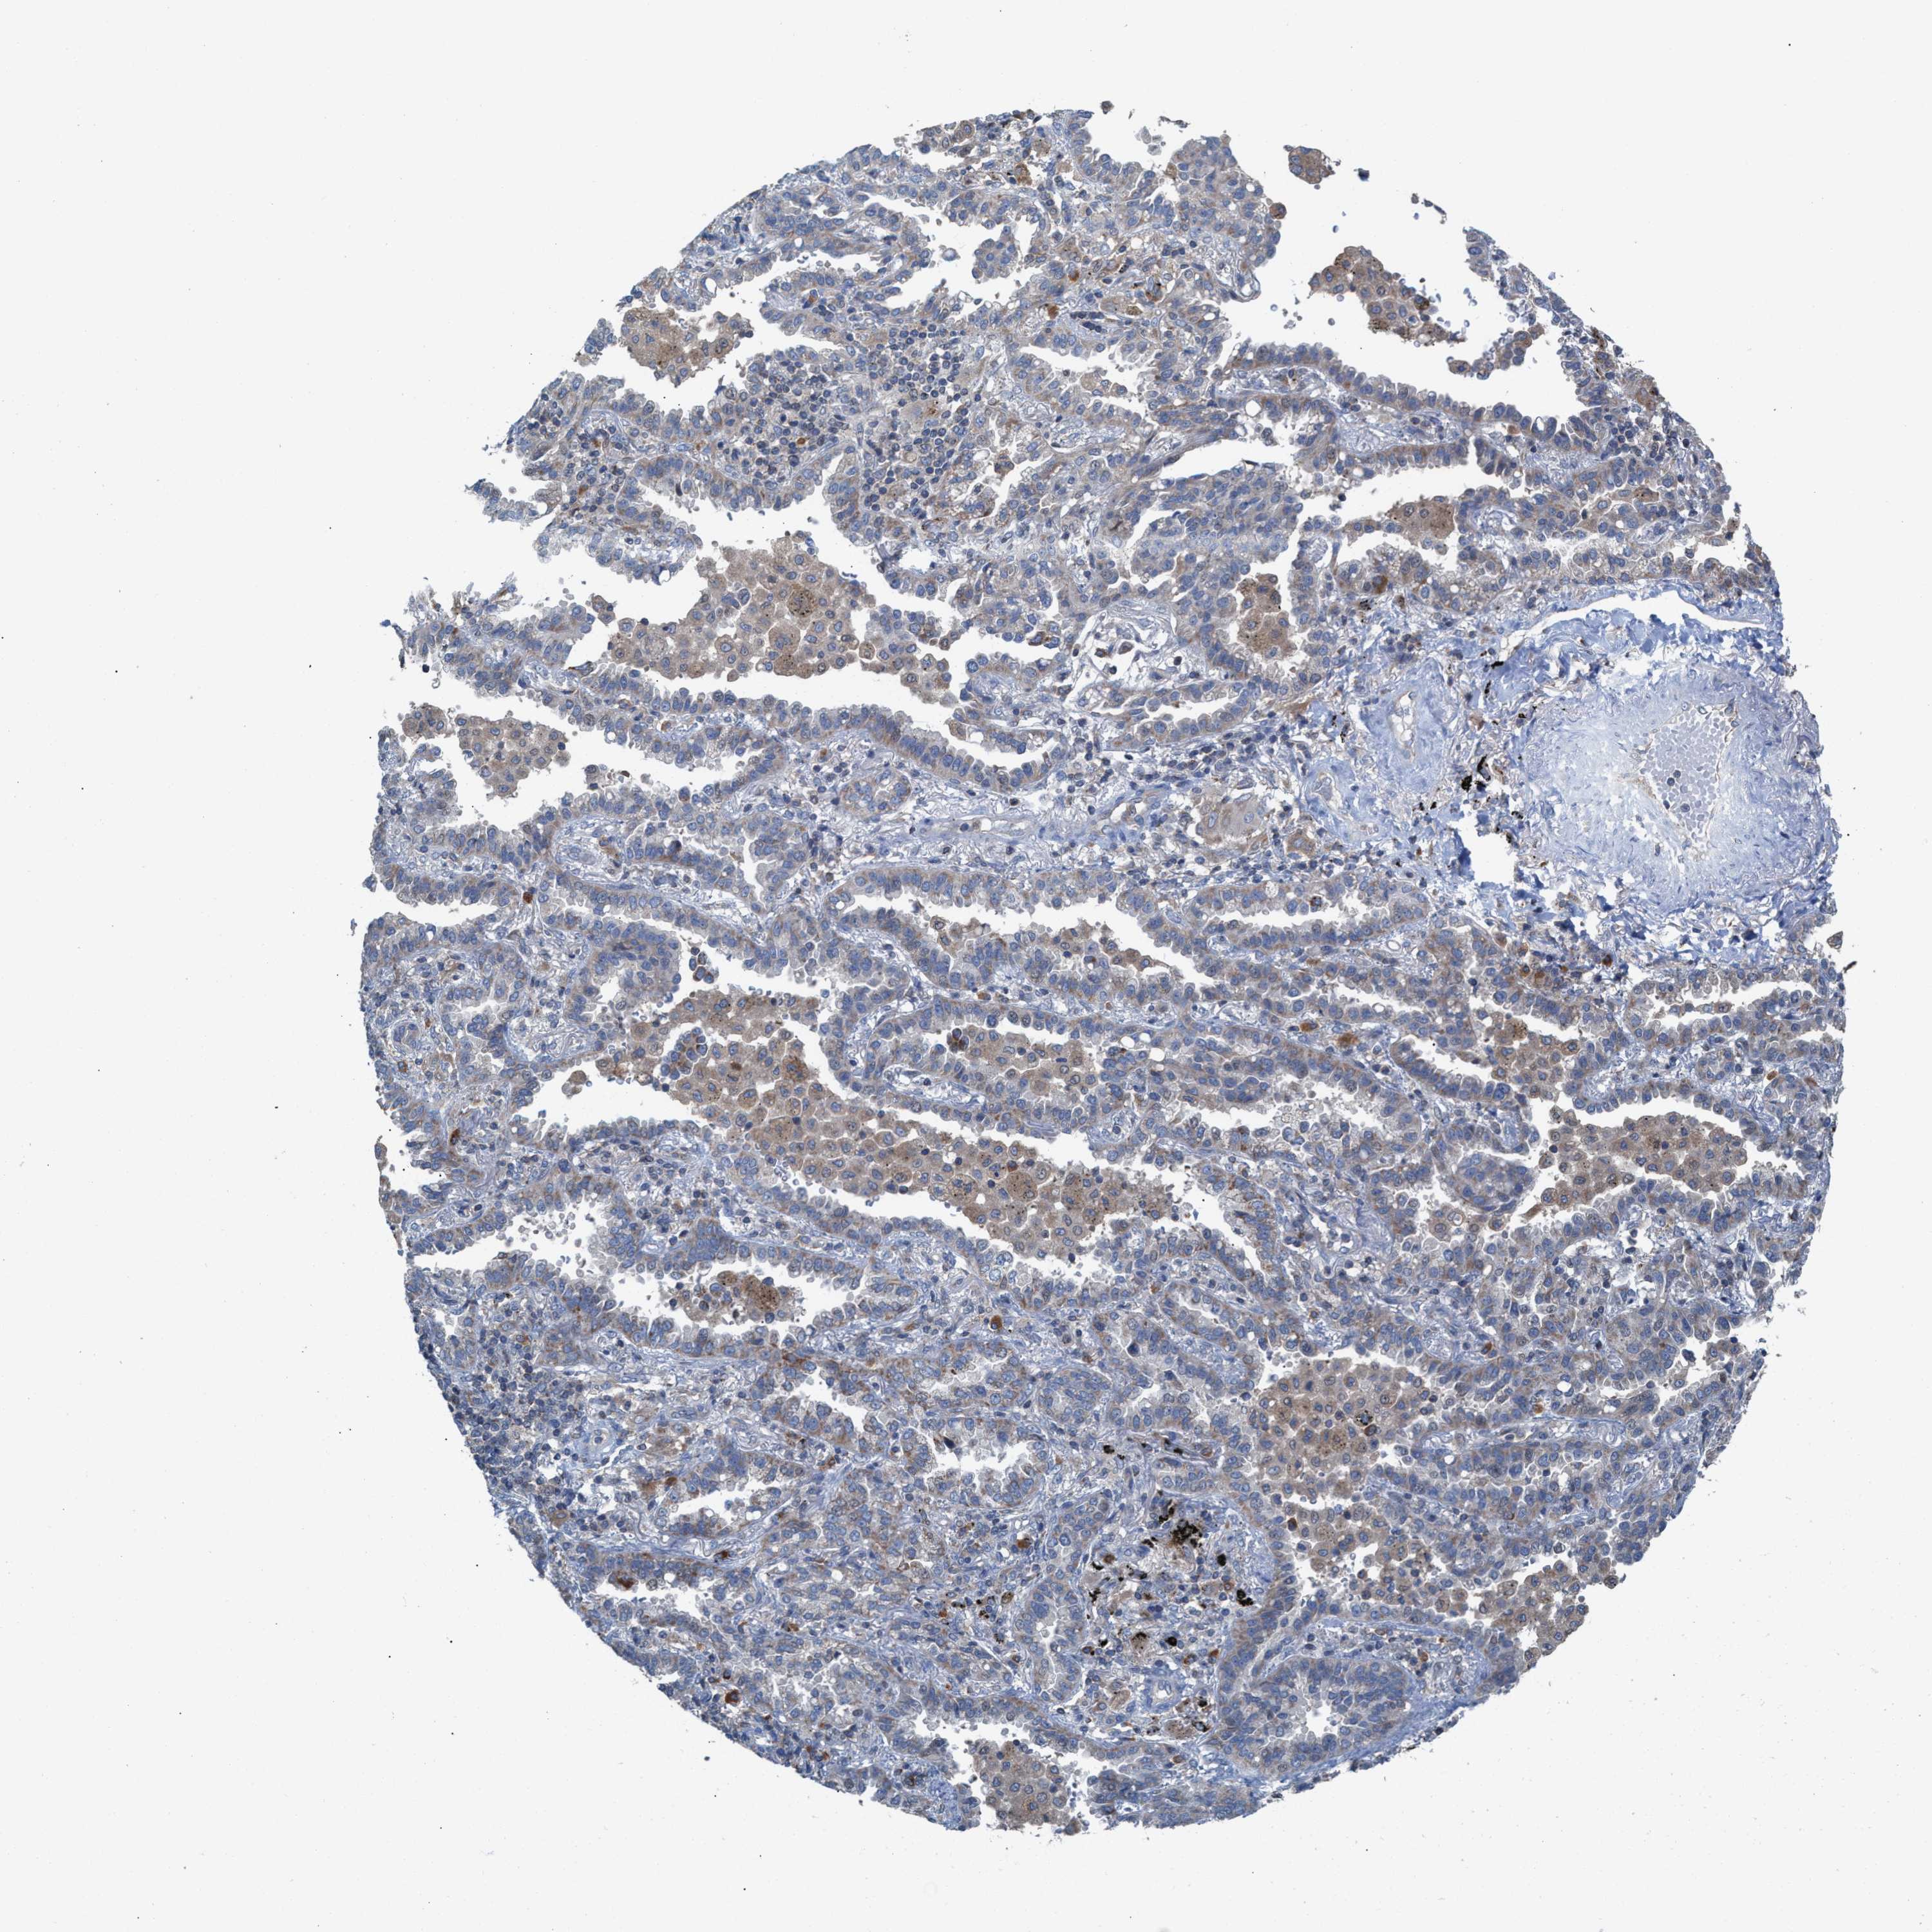

CANCER LUNG CANCER Show tissue menu

LUAD TCGA LUAD VALIDATION LUSC TCGA LUSC VALIDATION PROTEIN LUAD CPTAC PROTEIN LUSC CPTAC PROTEIN EXPRESSION

ANTIBODIES

AND

VALIDATION